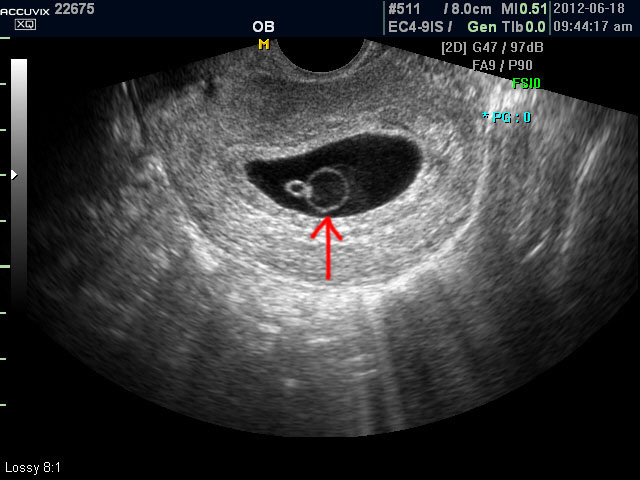

아래는 유산과 관련된 초음파 사진으로 위 사진은 유산기가 있다고 하는 경우 (의학적으로는 절박유산)의 사진이고 아래의 사진은 고사 난자라고 하여 태아가 정상적으로 형성되지 못한 유산의 사례입니다.

초음파 검사에서는 정상 임신으로 진단된 후 아기집 (태낭. G-Sac)이 보이지 않거나 평균 임신 주수에 비하여 아기집이 상당히 작을 때, 그리고 임신 8주 이후에 태아 심박동이 없는 경우에 유산일 가능성이 높다고 판단합니다.